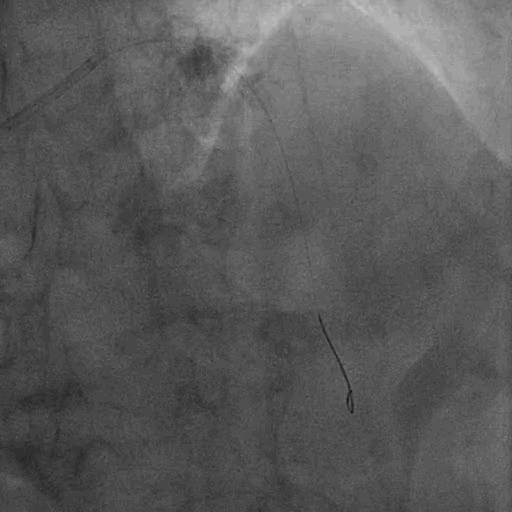

顺利跨瓣后,选取20mm球囊180bpm频率下快速起搏预扩。显示无漏,左右冠血流未受影响,考虑按照既定策略,选择Venus A 26型号瓣膜植入。

预扩

由于该患者轻度横位心,且为前后位二叶瓣,输送系统跨瓣存在一定困难,与会专家和术者一致考虑使用Snare技术。在右冠窦猪尾的指示和圈套器的辅助下,瓣膜输送系统输送至窦底,开始释放。在确认位置后,术者保持当前张力,快速一次性释放。

释放